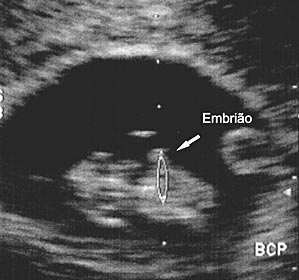

Semana 7

Reprodução O sexo é decidido na sétima semana de vida do embrião, apesar de ser determinado no momento da fecundação. Nesse período é comum não engordar ou até perder peso.” O bebê O sexo é decidido na sétima semana de vida do embrião, apesar de ser determinado no momento da fecundação. Nessa fase o tamanho do bebê é de cerca de 25 mm, o coração dele bate mais ou menos 150 vezes por minuto e já estão definidos os olhos, nariz, lábios, orelha, órgãos internos e sistema nervoso central. Fofo, né?